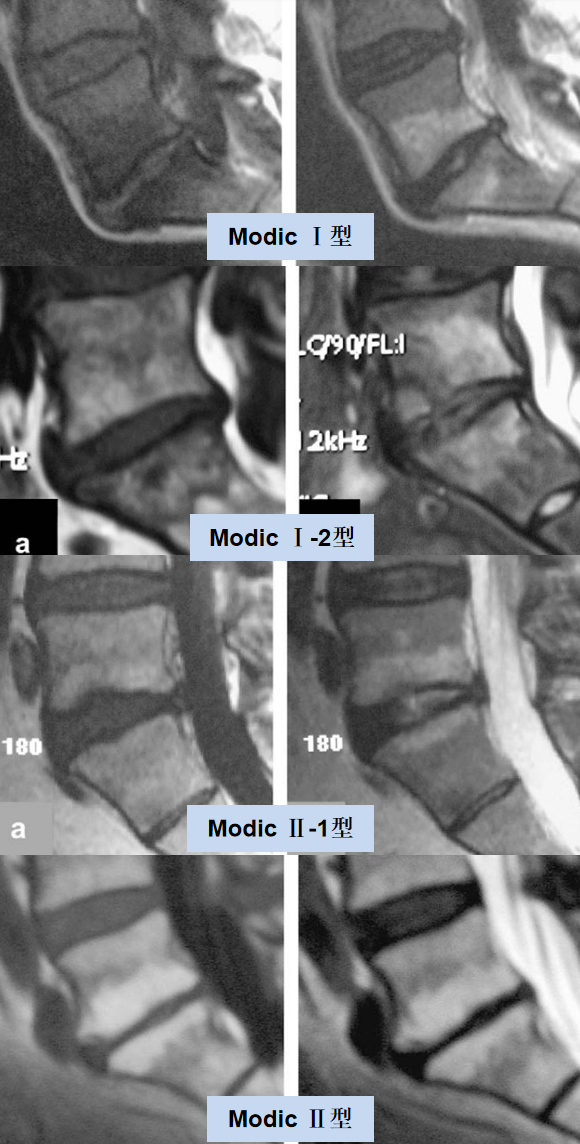

目前最常用的 Modic 改变分型是 1988 年 Modic 等提出的经典分型:

Ⅰ 型代表急性炎症和水肿改变,在 T1WI 呈低信号而 T2WI 呈高信号;

Ⅱ 型代表骨髓的脂肪变性, 在 T1WI、 T2WI 均呈高信号;

Ⅲ 型代表终板下骨硬化,在 T1WI、 T2WI 均呈低信号。

临床上,Modic 改变以 Ⅱ 型最多见,Ⅲ 型少见。

2009 年,Fayad 等在经典分型基础上,提出混合型的分型:

Modic I-2 型:混合性水肿和脂肪改变,以水肿为主;

Modic II-1 型:混合性水肿和脂肪改变以脂肪变性为主。

其实,Modic 改变是一个动态的病理过程,Ⅰ 型和 Ⅱ 型 Modic 改变随着时间的推移可以相互转换。

Mitra 等采用 MRI 纵向研究发现,在大多数情况下,Ⅰ 型 Modic 改变要么转化为 Ⅱ 型,要么变得更广泛。此外,约 20% 的病变为混合型,此混合型其实是同一病理过程的不同转变阶段。